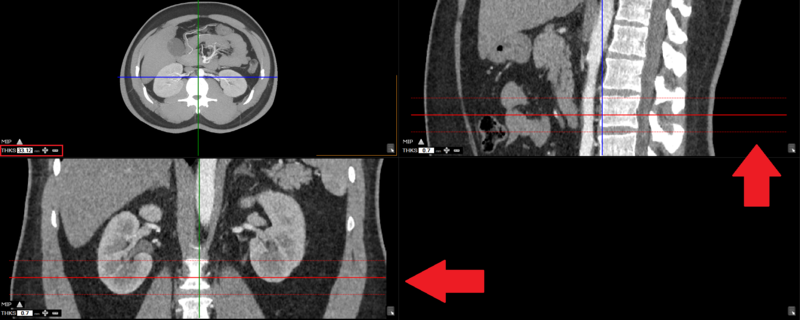

The user can view the thickness on the other views (windows):

The user can increase / decrease thickness by using the "+" and "-" or manually entering in the desired value.

The thickness is used to calculate intensity projection for that area.